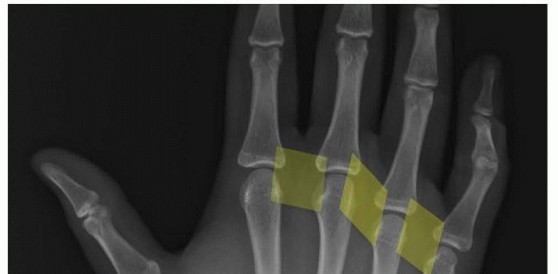

18 MIN READ Open Reduction and Internal Fixation of Ulnar Styloid, Head, and Metadiaphyseal Fractures يناير 2023 Read More